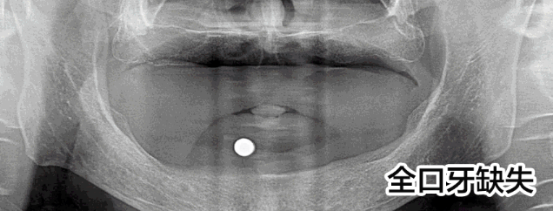

先天性牙缺失修復(fù)案例

趙先生先天性發(fā)育異常導(dǎo)致全口牙缺失,才36歲就掉了好幾顆牙,為此趙先生痛苦:“聽說這是一種病,發(fā)病概率小,但不知道怎么就被我攤上了。我還這么年輕就缺了這么多顆牙,真的很奔潰!”

趙先生的遭遇讓人同情,他尋找了多家醫(yī)院都被告知他由于牙齒缺失沒有進行及時修復(fù)導(dǎo)致他的牙槽骨萎縮,再加上本身骨量不足,無法進行牙齒種植。牙齒的問題讓趙先生一度有了輕生的念頭。而這次他通過新聞知道亞洲種植牙大師劉斌元教授來到福州,就抱著希望來到科爾。

劉斌元教授在為趙先生進行一系列的檢查后說:“這位患者要做種植牙手術(shù)的話的確復(fù)雜,但是也并非說不能種植,就是操作起來難度大?!?

趙先生的手術(shù)順利,種植牙齒后他覺得整個人都活過來了。

“當(dāng)時只是覺得人很舒服,一下子就放松了,之后腦子就是一片空白,手術(shù)進行的很快,從進入種植間到至后一顆種植牙的植入,只用了短短3個小時”,三分鐘改變了趙先生的一生,趙先生感激劉斌元教授:“如果沒有劉斌元教授為我進行手術(shù),我都不知道接下來該怎么辦?,F(xiàn)在說什么都不能表達(dá)我的感激之情,但還是要對劉院長說一聲謝謝!”

首先,像趙先生這樣的先天性發(fā)育不良造成的全口牙缺失的病例本身就是很罕見的,可以說是幾十年難遇。其次,全口牙缺失本身就屬于牙科領(lǐng)域中難的一種技術(shù)。沒有先進的高精口腔CT技術(shù)的保障,在傳統(tǒng)的診療條件下,很難手術(shù)的。因而,在硬件、設(shè)備、技術(shù)還不成熟的情況下,并不是所有醫(yī)院都能完成這種病例的調(diào)節(jié)。因此,在做全口牙種植前,選擇正規(guī)的醫(yī)院和臨床經(jīng)驗豐富的醫(yī)生,是保障手術(shù)成功的先決條件。